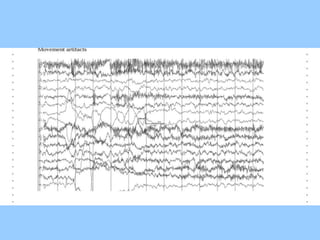

1. The document discusses EEG patterns and findings in various neurological conditions seen in children. It includes descriptions of normal EEG findings as well as abnormal patterns seen in conditions like absence seizures, West syndrome, benign childhood epilepsy with centrotemporal spikes, Lennox-Gastaut syndrome, non-convulsive status epilepticus, subacute sclerosing panencephalitis, and herpes encephalitis.

3. International standards for EEG electrode placement and recording parameters are reviewed. Characteristics of different EEG waves, amplitudes, and patterns are described.